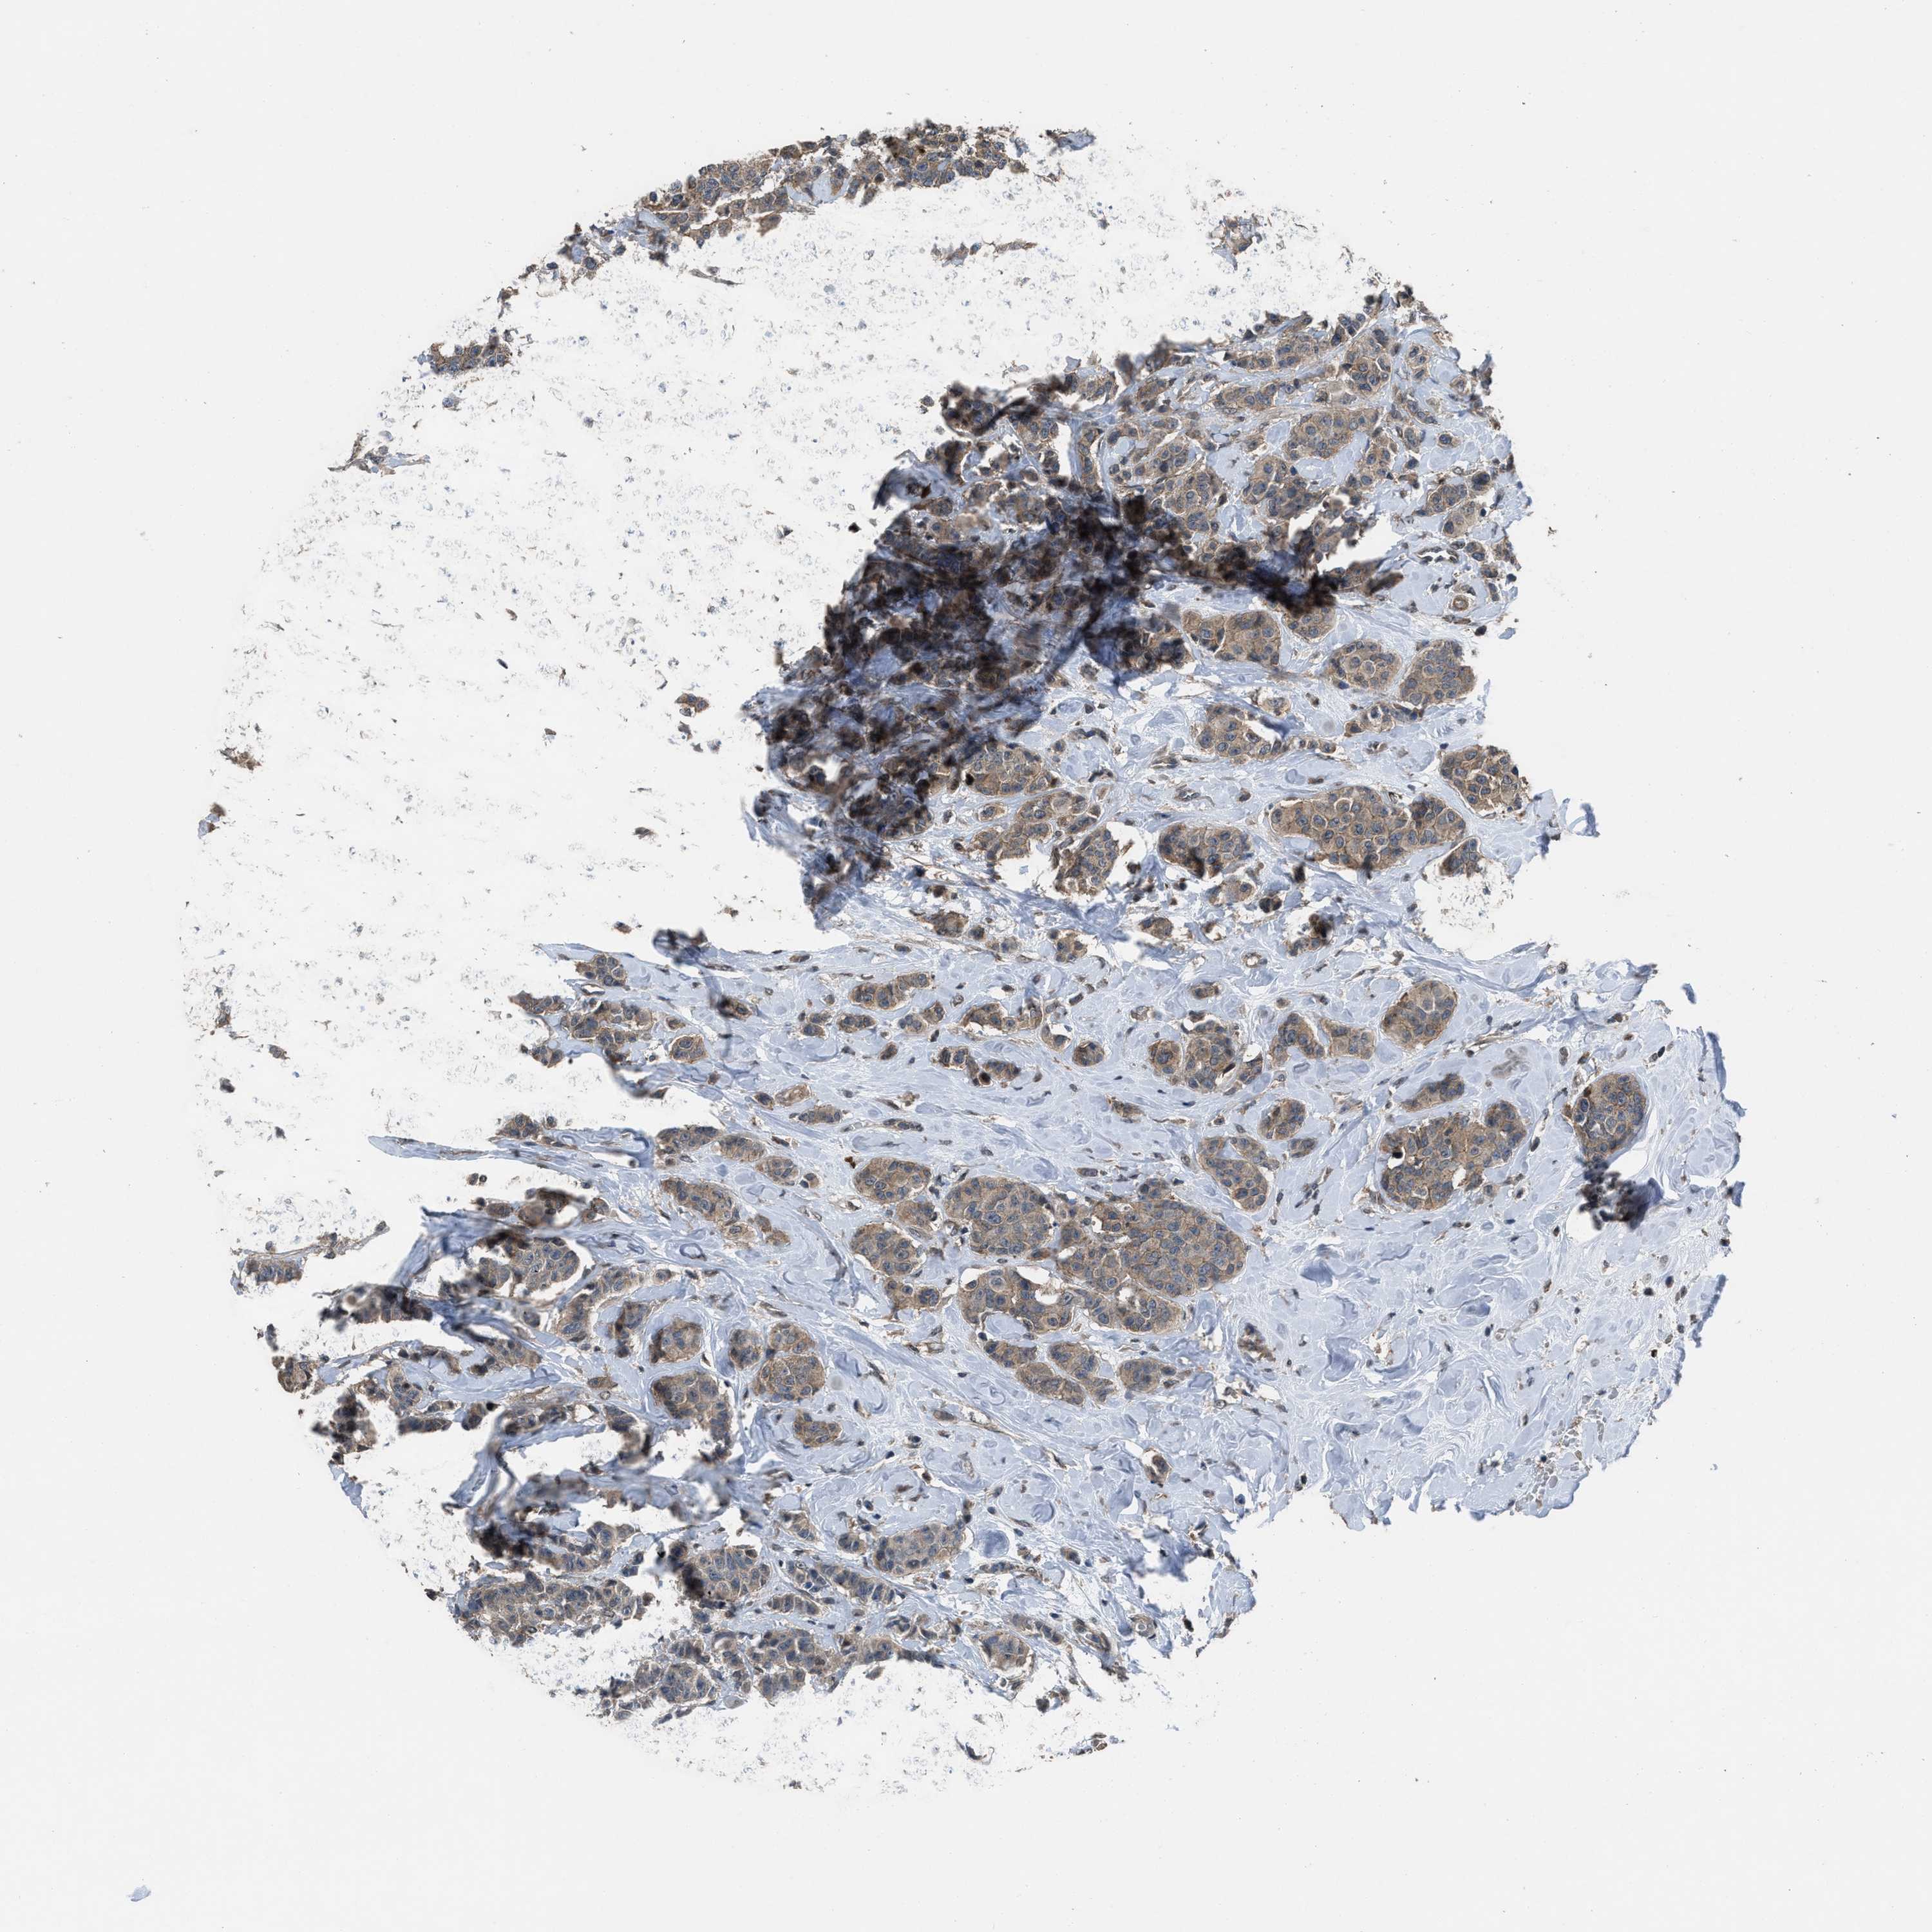

CANCER BREAST CANCER Show tissue menu

BRCA TCGA BRCA VALIDATION PROTEIN EXPRESSION